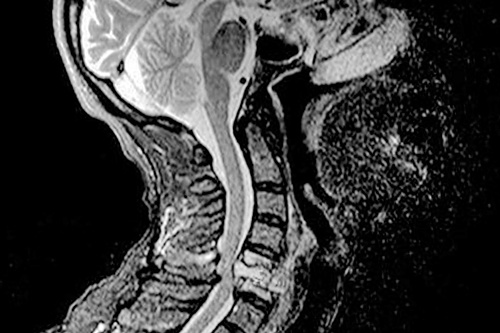

При подозрении на невралгию важно немедленно обратиться в медицинское учреждение для диагностики. В ходе обследования могут быть назначены рентген шейных позвонков, компьютерная томография и магнитно-резонансная томография.